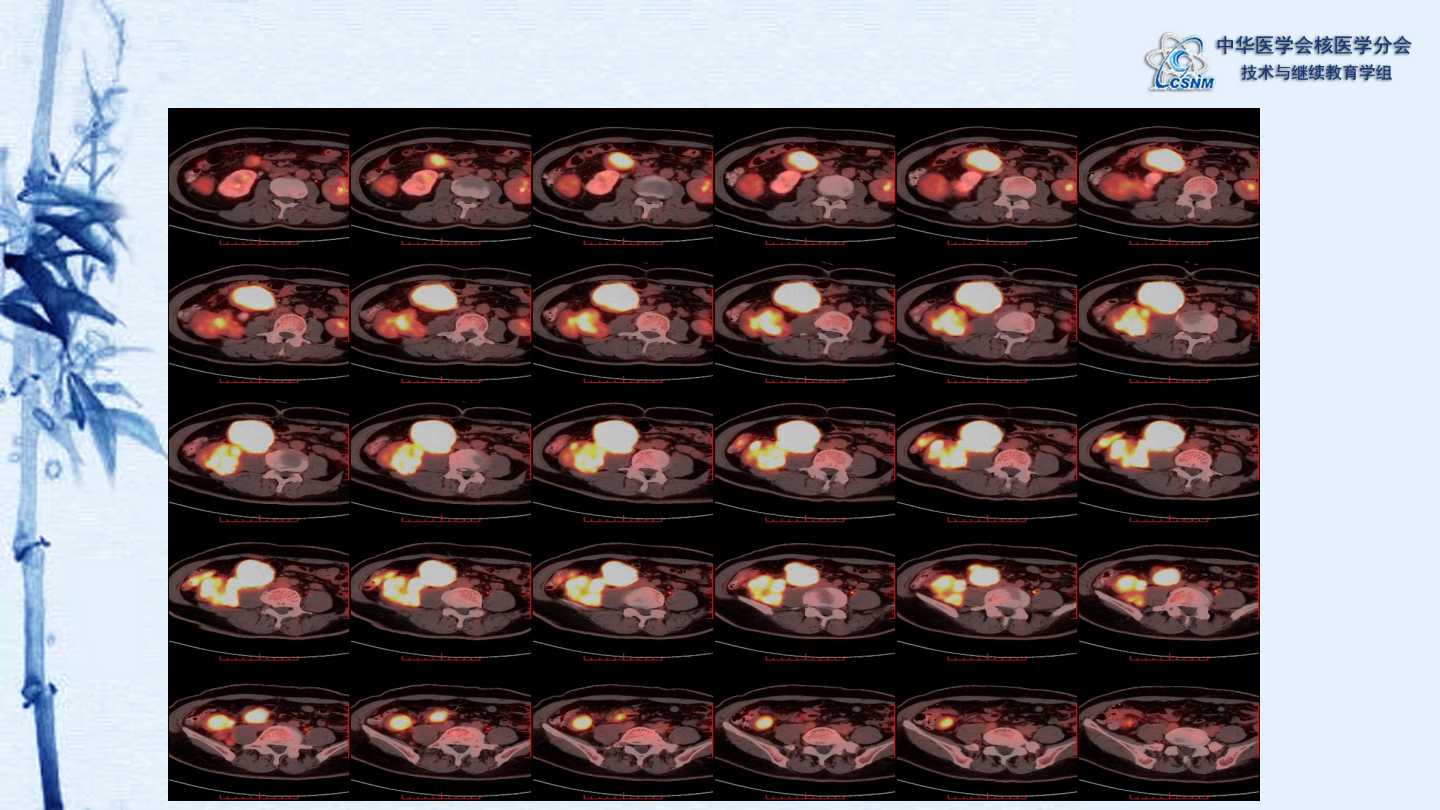

【CSNM继教学组】病例E51-邢岩-结肠炎性肌纤维母细胞瘤18F-FDG PET/CT显像